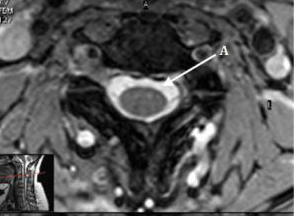

: Image 19 is an example of a:

Axial cervical spine